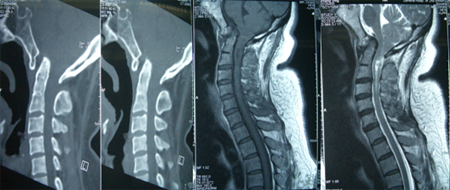

女性,43岁,头痛头晕3年,右上肢肌萎缩3月。查体:短颈、发髻低,颈部过伸、过屈位持续5分钟出现头痛头晕、右上肢麻木;右上肢肌萎缩,肌力4级,病理征阳性。影像学资料显示寰枢关节半脱位、颅底凹陷、颈2-3棘突分隔不全、小脑扁桃体下疝入椎管达C1-2水平(Chiari I 畸形)、脊髓空洞症。

术式:枕颈减压、枕大池成型术。

术后患者没有新出现的神经功能缺失,头痛头晕和肢体麻木改善,一年后右上肢肌力有所恢复。

专家评点:较全面的寰枕畸形会导致延颈髓腹背侧的压迫,从而引起相应的临床症状。治疗应在保证稳定性的前提下,尽量做到充分的延颈髓减压,手术可分为单纯颈前路内陷齿状突切除,单纯颈后路枕颈减压、侧块螺钉固定,或颈前路牵引复位、后路寰枕融合术。该患作了单纯颈后路的枕颈减压和枕大池成型术,术后临床症状即获充分改善,所以具体术式可根据患者首发症状和体征进行遴选。